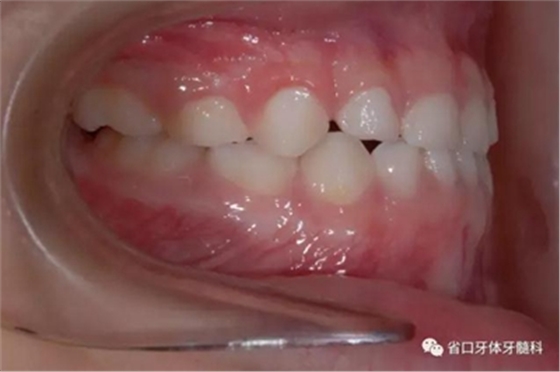

圖5 左側(cè)45度牙相

圖6 右側(cè)45度牙相